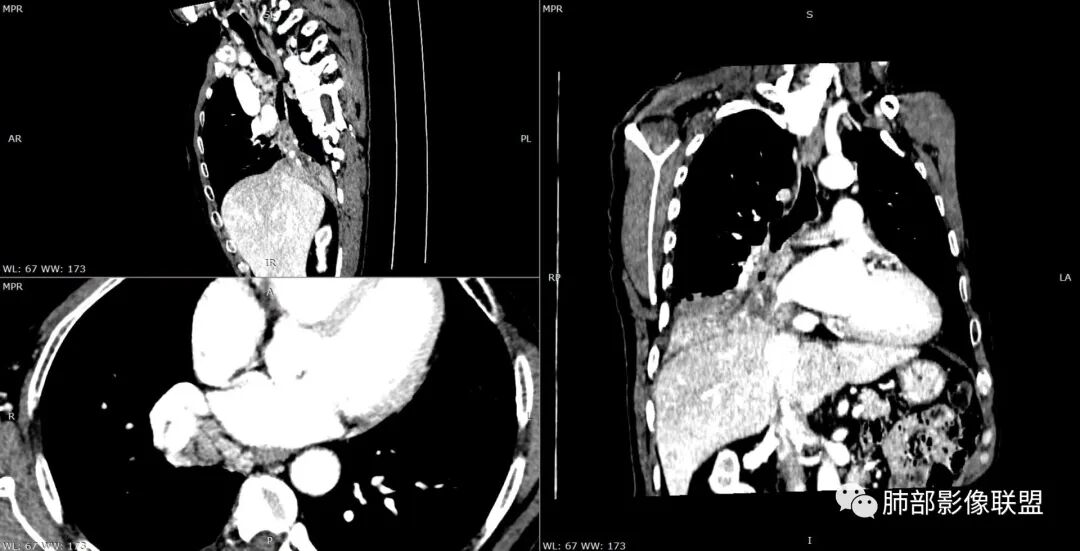

南边老师分析:病灶起源于中间段支气管内侧壁,腔内占位,恶性没问题,远端都是阻塞性炎症,标红色的圆圈是肿瘤原发位置。

1.支气管腔内强化结节影,管腔阻塞,阻塞性肺炎(肺炎、肺不张),符合引流途径的肺门纵隔淋巴结肿大。符合恶性新生物判断,腔内结节影均匀强化,一般也不符合异物或结核等肉芽肿性炎。

最常见的显然是鳞癌,这点相当重要,管腔内结节,阻塞彻底,阻塞性肺炎,又是老年男性患者等等。

注意,阻塞性肺炎的实变区或膨胀不全的肺组织可以强化较显著,肺血管保持自然完好,有时可以衬托出肺门方向的肿块边缘。